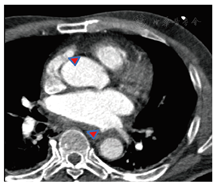

病例3患者女性,73岁。7 d前于外院行房颤射频消融术,主因"吞咽困难伴发热2 d"转入我院。患者2 d前无明显诱因出现吞咽困难,伴吞咽异物感,发热,体温最高37.8 ℃,于当地医院就诊,血常规示白细胞计数(11.73×109/L)及中性粒细胞(0.723)轻度升高,予头孢哌酮舒巴坦钠抗感染治疗后症状无明显缓解。14 h前上述症状加重,伴胸部不适,行胸部CT检查示心包腔积气,超声心动图示:双心房扩大(左心房57 mm×55 mm× 77 mm;右心房45 mm×64 mm)、二尖瓣重度反流(反流面积10.3 cm2),疑诊"左心房食管瘘",遂嘱禁食禁水,予奥美拉唑持续静脉泵入,并迅速转往我院。当日凌晨入院后患者一般情况尚可。心电图未见异常,复查血常规示:白细胞计数(16.5×109 /L)及中性粒细胞(0.861)持续升高,复查血生化示肌酐(156.5 μmol/L)及肌钙蛋白(0.110 µg/L)较前升高。血培养示革兰氏阳性菌。急查左心房CTA未见龛影或瘘管形成,但可见心包腔内主动脉根部积气,嘱患者吞钡使食管显影后见食管紧邻左心房后壁迂曲走行,同时伴有双侧胸腔积液(图4),头颅核磁共振成像序列检查示额叶新鲜梗死灶,初步诊断考虑"心包食管瘘"可能。遂继续禁食禁水、抑酸、抗感染治疗,纠正水电解质紊乱。多学科会诊后考虑"心包食管瘘"及"左心房食管瘘"可能性大,但患者心功能不全、肾功能不全,导管消融术后时间短,外科手术风险大,同时术后感染可能难以控制,建议暂继续当前治疗,可择期行手术修补,密切观察病情变化。入院后12 h,患者体温再次升高至37.7 ℃,心电图示窦性心动过缓。后患者突发尖端扭转性室速及Ⅲ度房室传导阻滞,对异丙肾上腺素及多巴胺均不敏感,迅速转入冠心病监护病房(coronary care unit, CCU)并置入临时起搏器,心电图可见起搏信号但未见心室夺获,随后患者死亡。